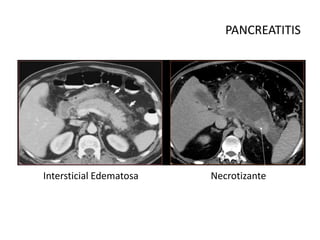

•Intersticial

Edematosa

•Necrotizante

Fases y Presentación

Intersticial Edematosa Necrotizante